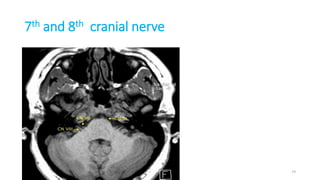

7th and 8th cranial nerve

74

Internal auditory meatus

Content

• Labyrinthine artery

• Facial nerve (VII),

• Vestibulocochlear nerve (VIII)

1. Magnetic resonance imaging (MRI) is the gold standard

technique in the study of the cranial nerves

2. Steady-state free procession (SSFP) images are the best

sequences for the visualization of the cisternal segments

showing dark cranial nerves against a background of bright

cerebrospinal fluid (CSF)